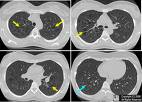

(7)肺 LCH的肺部病變可做為全身病變的一部分,也可能單獨存在,即所謂原發性肺LCH。任何年齡都可出現肺部病變,但兒童期多見於嬰兒,表現為輕重不等的呼吸困難,缺氧和肺的順應性變化。重者可出現氣胸、皮下氣腫,極易發生呼吸衰竭而死亡。肺功能檢查常表現限制性損害。

(5)X線檢查 肺部X線檢查多為肺紋理呈網狀或網點狀陰影,顆粒邊緣模糊,不按氣管分支排列。有的肺野呈毛玻璃狀,但多數病例肺透光度增加,常見小囊狀氣腫,重者呈峰窩肺樣。可伴間質氣腫、縱隔氣腫、皮下氣腫或氣胸,不少患者可合併肺炎,此時更易發生肺囊性改變,肺炎消退後,囊性變可消失,但網粒狀改變更為明顯,久病者可出現肺纖維化。骨骼X線改變見前述。